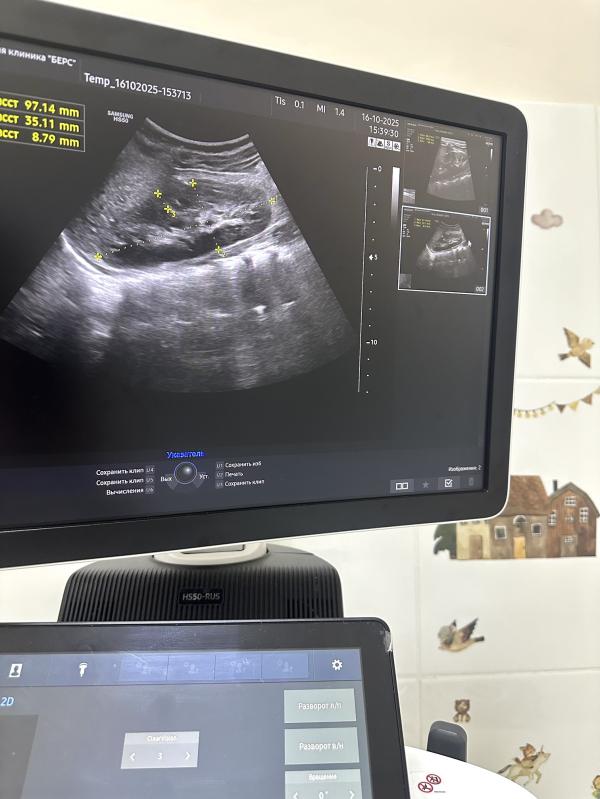

Недавно ко мне обратилась мама девочки двухлетнего возраста на плановое УЗИ органов брюшной полости и почек. Исследование показало отличные результаты по органам живота, однако с почками возникла интересная ситуация...

При осмотре обнаружилось значительное увеличение правой почки ребёнка, а левая оказалась отсутствующей. Несмотря на тщательные поиски, обнаружить её так и не удалось. В конце процедуры мама упомянула мимоходом, что одной почки действительно нет. Этот пример наглядно демонстрирует важность регулярных медицинских проверок даже тогда, когда кажется, что всё хорошо!

* на первом снимке как раз почка малышки, на втором - мое заключение узи, на третьем - нормы размеров почек